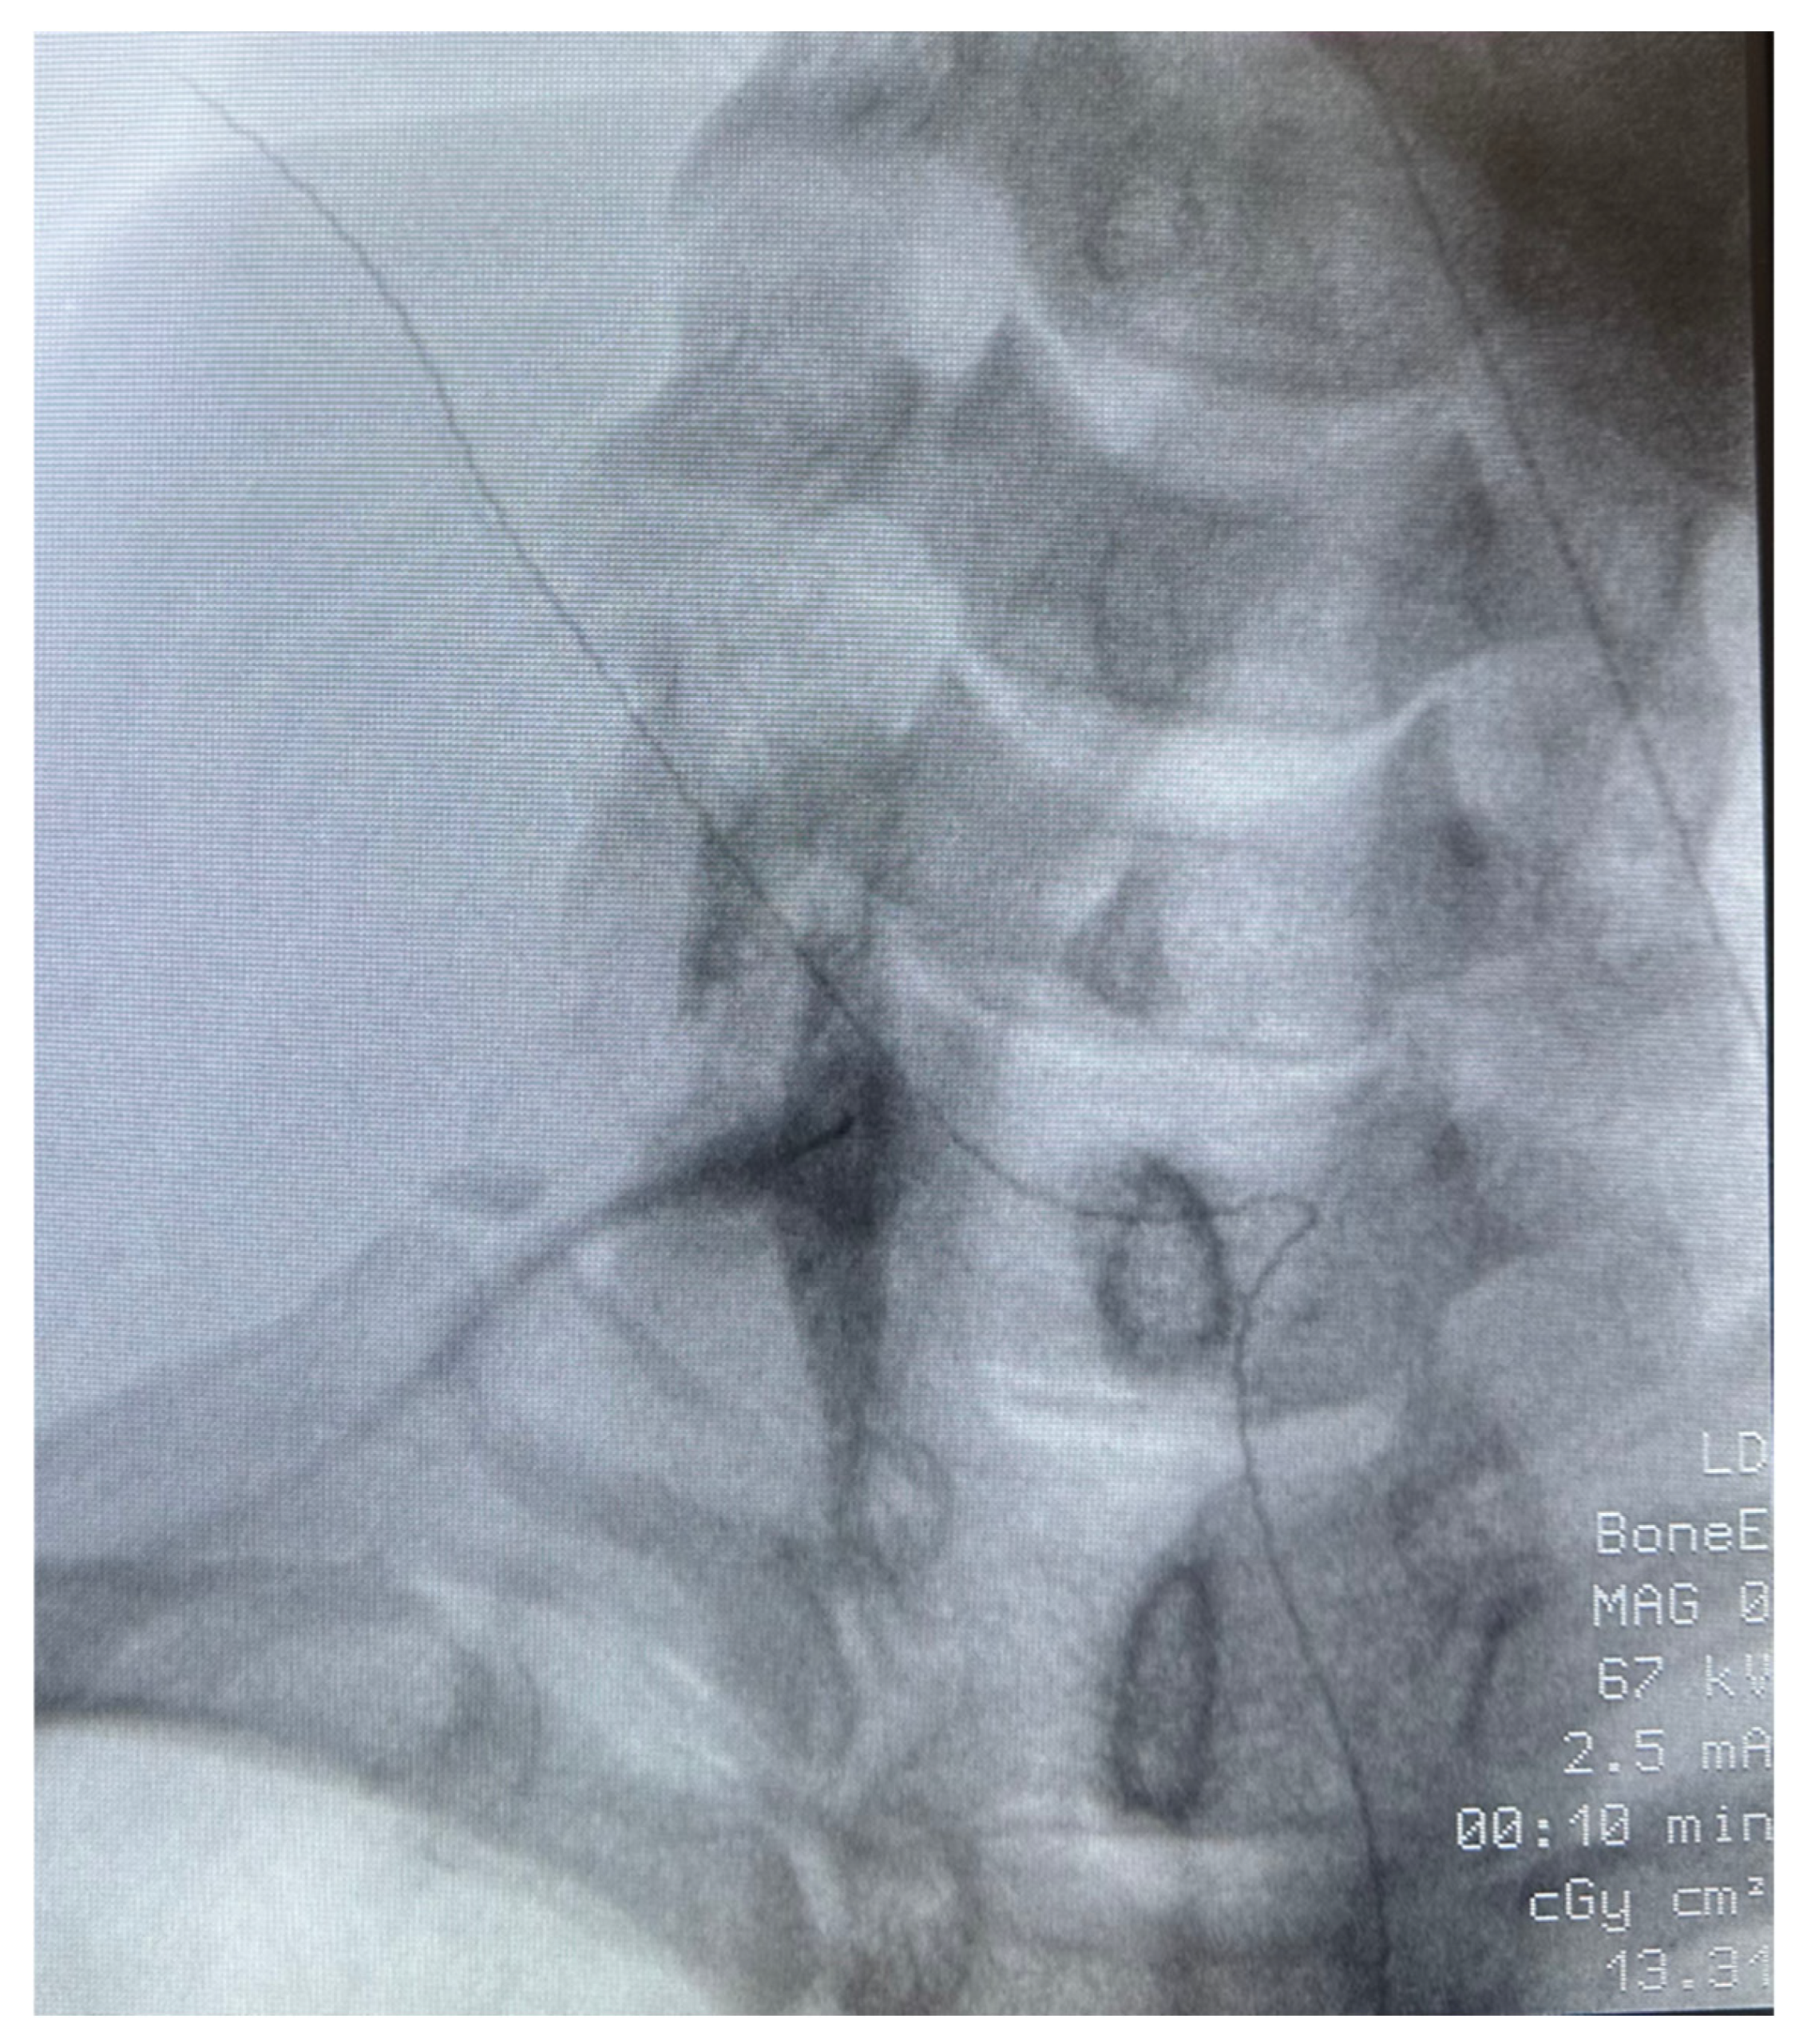

Figure 2. Fluoroscopically guided right stellate ganglion block (Patient #1). The same technique was used for Patient 2 and 3. Patients were placed supine with neck in an extended position. The neck and shoulder area were prepped and draped in a sterile fashion. Using anteroposterior fluoroscopy, an image of the patient’s neck was obtained. The C6 transverse process (Chassaignac’s tubercle) was identified and marked. The skin over the area was topicalized with 1% lidocaine. The carotid artery and trachea were identified and palpated. Lateral traction on the carotid was placed, and a 25 gauge, 3.5 inch spinal needle was inserted and advanced, guided by fluoroscopy, to the target of the vertebral body and the uncinate process of C6. Once the target was reached, and after negative aspiration for heme, air, and cerebrospinal fluid, and in the absence of paresthesias, 1 mL of Omnipaque 180 mg/mL was injected to confirm spread along the stellate ganglion. A second aspiration was performed. When confirmed negative, 6 mL total of a mixture of dexamethasone 10 mg, lidocaine 2% with epinephrine, and bupivacaine 0.25% with epinephrine, was injected in 2–3 mL increments at the stellate ganglion, with frequent monitoring of signs and symptoms of intravascular injection.